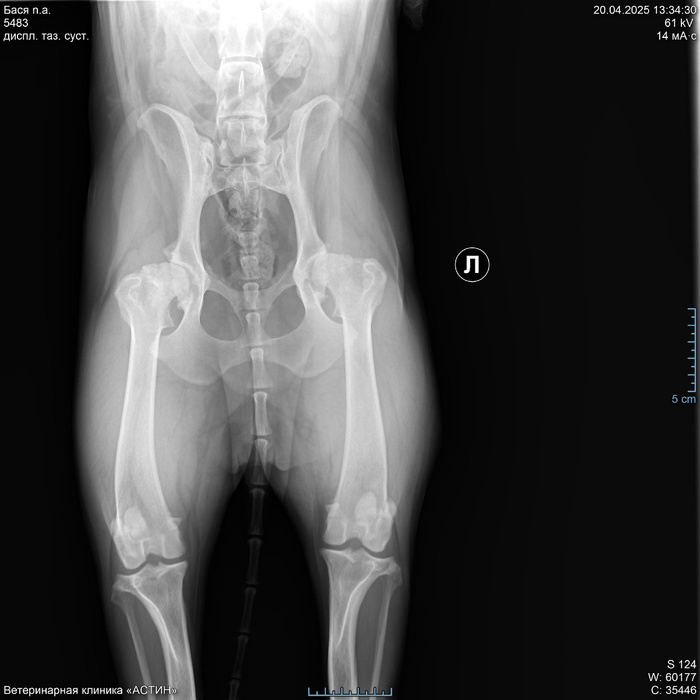

Протезирование ТБС (тазобедренного сустава) собаке. Часть 1

Пост НЕ рекламный, НЕ агитирующий и т.д. Все - лишь личный персональный опыт.

Зимой 2015 года мы подобрали на пустых дачах замерзающего щенка. Ну, точнее она сама подобралась, придя к нам. История спасения и приобретения этого сокровища - тема отдельного поста, здесь эта информация будет лишней. По итогу мы стали обладателями чистопородной дворняжки. Где-то года два назад мы начали замечать, что Бася иногда прихрамывает на заднюю лапу. Чаще всего это появлялось после долгого лежания на жестком. Похромает пару минут и все проходит. Собаку вроде сильно не беспокоит. Мы несколько раз при случае спрашивали ветеринаров про эту хромоту, но общий смысл ответов сводился к "отстаньте от собаки, это возраст". Вроде выглядело все логично. Особого дискомфорта нет, собака нормально гуляет, ест и прочие дела делает. На жестком спит редко, только летом в жару. Для профилактики периодически давали ей курсами хондропротекторы и на том успокаивались. Да и с возрастом она стала очень спокойной барышней, почти перестала играть с собаками. Так мы и жили спокойно, пока одним непрекрасным апрельским утром Бася с утра не отказалась идти. Она еле переставляла мелкими шажочками задние лапы. Да, потом она расходилась, но мы поняли, что что-то тут не то, срочно потащив ее уже на целенаправленный прием к хирургу.

2. Подготовка к операции

На приеме хирург покрутил и повертел лапы, сделал рентген и сообщил, что ТБС у Баси-то практически и нет. Суставы оба убиты в ноль. Мы, честно говоря, немного обалдели. У нас до Баси был немец и мы знали что такое дисплазия, хотя немец ушел на радугу все же на своих четырех лапах без операций. Но мы думали ,что мы знаем как выглядят больные суставы. Оказалось, что вот эта редкая хромота была вполне себе признаком. Тут мы виноваты, конечно, не досмотрели. Ну и хирургом нам были предложены три тактики дальнейшего лечения. Первая - оставить все как есть. Условно - приложить подорожник в виде все тех же хондропротекторов. Но толку от этого не было бы никакого, так, для собственного успокоения. Вторая - реабилитолог. Походить на плавания, занятия и т.д. Но по честному мнению врача в нашем случае это было бы чуть лучше, чем подорожник. Спасать там было нечего уже. Ну и третий - операция. В этом случае еще 5-6 лет активной жизни у собаки будет. Из минусов - цена. Описав все варианты, доктор отпустил нас, не склоняя и не агитируя ни в какую сторону. За что ему большое спасибо. Конечно, мы были шокированы и испуганы перспективами. Либо обрекать собаку на постоянную боль (а как оказалось, она испытывала постоянную боль уже очень давно) и риск в любой момент получить перелом или травму бедра от любого резкого движения, т.е., фактически, класть собаку спать, или собираться с силами и деньгами и делать операцию. Резюмирую, что решение оперироваться было принято нами с мужем единогласно, т.к. девочку нашу мы любим и хотим ей долгой и счастливой жизни. О нашем решении мы сообщили хирургу и он рекомендовал нам клиники, которые делают подобные операции в Москве. По сути, их всего две.

Наш выбор пал на клинику Медвет по нескольким причинам:

• Оперирующий хирург - один из авторов системы бесцементного эндопротезирования тазобедренных суставов у животных (все авторы - сотрудники этой клиники)

• Сеть клиник внушила больше доверия, чем одна клиника

• Пожизненная гарантия на операцию

• Ну и решающий фактор - при одинаковой примерно стоимости в Медвете ждать операции нужно было намного меньше времени.

В клинике мне дали электронную почту того самого автора системы Вилковыского Ильи Федоровича (для краткости далее буду писать ВИФ), на которую я и отправила письмо с фото рентгена и описанием проблемы. ВИФ отвечал быстро, очень подробно. Рассказал об операции, о нюансах, сообщил стоимость и перечень анализов, дал ссылку на сайт, где все рассказано про операцию и сами протезы. В итоге записались мы на 16 июня 2025 на операцию, внеся предоплату в 50 т.р.

Оперируют только по одному суставу за раз. Восстановительный период - 60 дней до контрольного рентгена. Но самый критичный - первый месяц.

Дней за 5 до операции мы пошли сдавать общий анализ крови, биохимию и ЭХО. По ЭХО вопросов не было, а вот биохимия пришла с хилезом. Направив данные ВИФ, мы были переадресованы анестезиологу, которая дала комментарии по результатам и направила на пересдачу биохимии с узи брюшной полости. И, хотя нам грозил срыв операции, такой обстоятельный и серьезный подход внушал оптимизм. Слава богу по узи все было хорошо для нашего возраста, кровь пришла почище и нам дали добро на операцию.